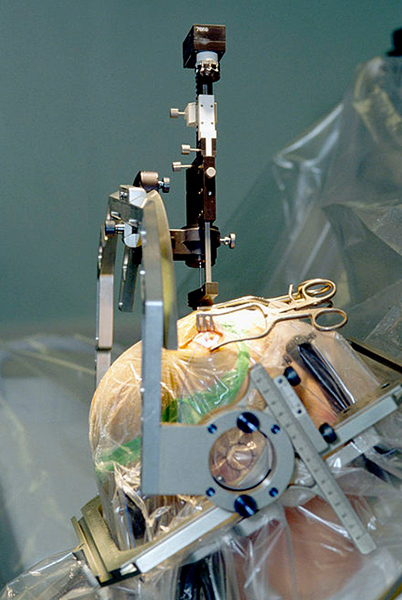

(图片来源:Pixabay)

在《公共科学图书馆·计算生物学》(PLOS Computational Biology)上发表的一项研究中,一名脑瘤患者在肿瘤切除前接受了皮层脑电电极阵列的安置,以定位癫痫发作并绘制大脑功能图。每一次电极相互作用都需要新算法对数百到数千个时间点进行研究。

用于帕金森病手术中,将电极插入大脑基底节的立体定向装置 (图片来源:维基百科)